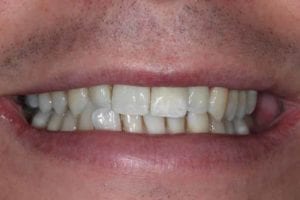

Same Day All on 4 Dental Implants Treatment

This patient had missing teeth and the those that remained were failing. After discussing with the patient, it was decided to remove the failing teeth and rehabilitate with same day all on 4 dental implants.

This treatment is usually carried out in 1 day (after a few preparatory appointments for moulds, x-rays, etc). The failing teeth were removed and implants place on the same day, with a temporary bridge (fixed teeth) attached also on the same day. Following a period of 3 to 6 months, moulds were taken and the definitive bridge placed